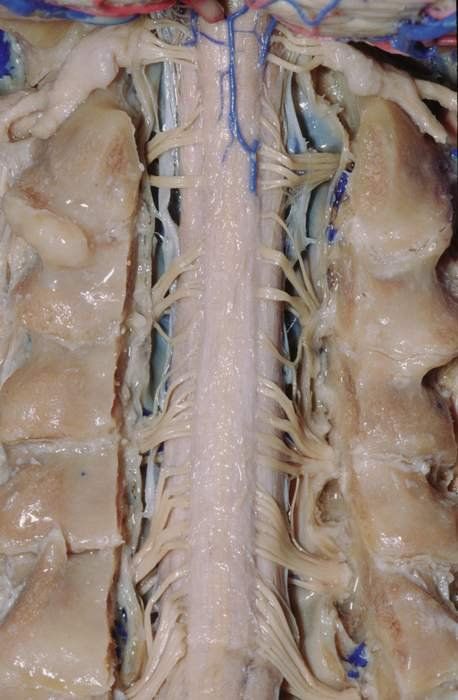

혐오) 인간의 척수신경 모습

(실제 인간척수신경)

(염색해서 구분한 신경계 사체 교보재)

마치 컴퓨터 서버같이

복잡하면서도 정교하게

나뉘어있고 분류되어있음

불의의 사고로

지저분하게 찢겨나간다면

사실상 연결시키는게

불가능한 이유

모두 사고에 조심합시다.